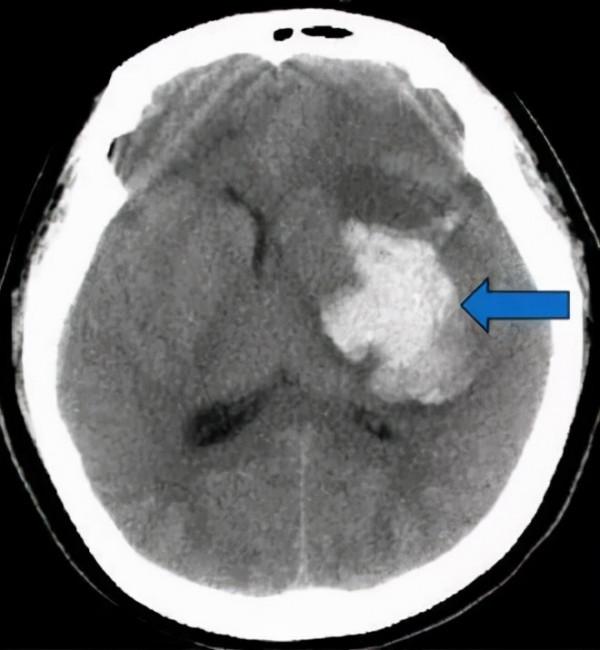

10天前,他突發昏迷被送到醫院,入院測量血壓240/130mmHg,腦CT提示大面積腦出血。就算做了開顱手術,可是他還是沒醒過來,住進了監護室,一住就是10天。醫生多次和老父親溝通,說患者醒過來的可能性非常小,一直住下去可能花不少錢,最後還可能人財兩空。

腦出血最主要的原因就是高血壓不控制,腦出血死亡率很高,30-40%的腦出血會在急性期死亡,還有很多人會留有後遺症:偏癱失語,半身不遂,長期臥床等等。